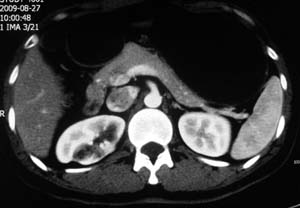

以下是引用子期在2010-3-19 20:47:00的发言:[br]血管畸形的ct增强应该有明显强化,本例并不相符合。本例双肾局部的略低密度影,累及肾盂,局部皮质明显变薄、内陷,增强扫描有轻度的强化,应考虑为炎性病变,患者为年轻男性,累及双肾的感染以结核较常见,可以没有明显的临床症状,尿中有时候也并不能查出什么;肾脓肿常有明显感染中毒症状,本例不符,另外一般的肾盂肾炎或肾小球肾炎通过小便就可确诊,其它还不能排除的是黄色肉芽肿性肾盂肾炎,然而单凭ct一般也很难鉴别。